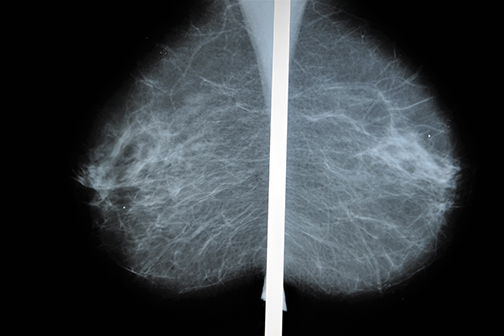

The Gulf South National Cancer Institute (NCI) Community Oncology Research Program (NCORP), led by LSU Health New Orleans with its partner institutions Mary Bird Perkins Cancer Center, LSU Health Shreveport and Ochsner, has enrolled nearly 2,000 women in a breast cancer screening trial that will help determine the best ways to find breast cancer in women who have no symptoms. Under the direction of the principal investigator Augusto Ochoa, MD, at the Stanley S. Scott Cancer Center, LSU Health New Orleans has enrolled more than 900 participants at University Medical Center, with more than 200 at Mary Bird Perkins Cancer Center and more than 600 at LSU Health Shreveport. More